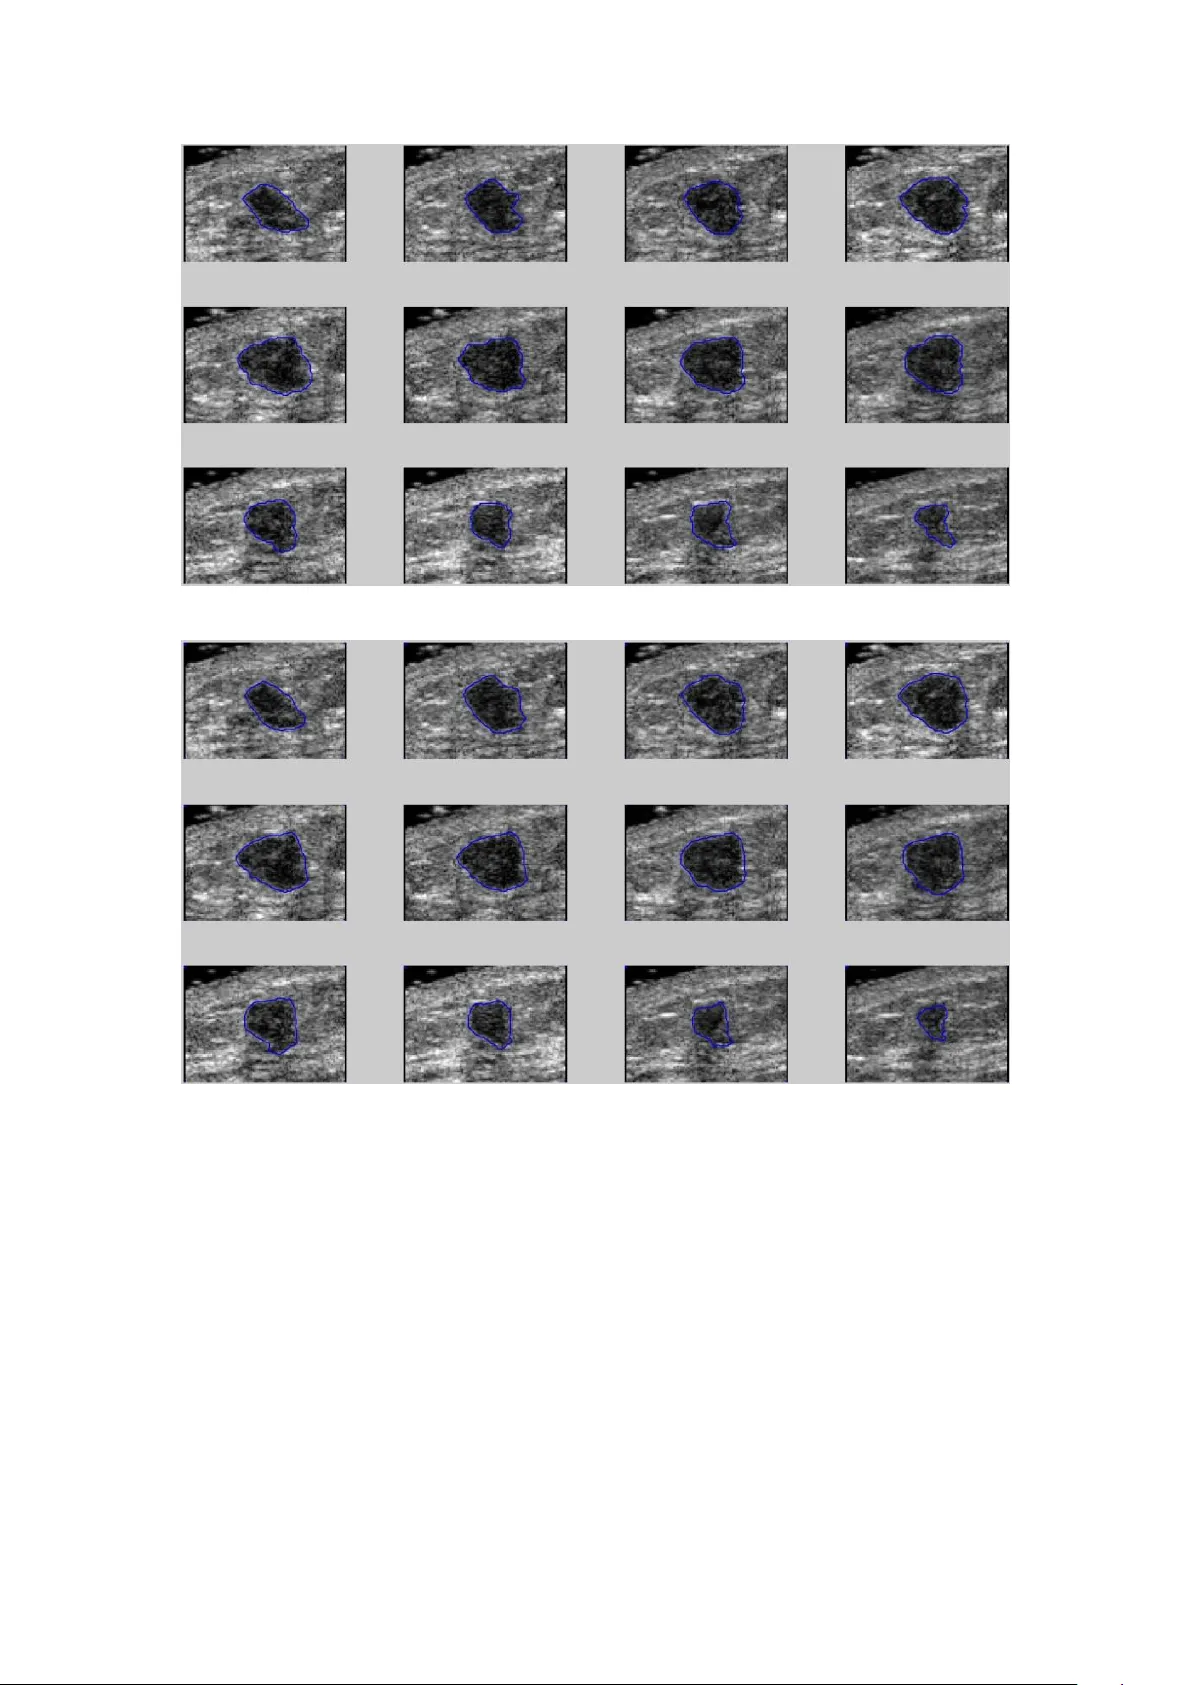

본 연구는 3차원 초음파 영상에서 유방 종양을 자동으로 분할하기 위해 3D 영역 성장으로 초기 윤곽을 만든 뒤, Chen‑Vese 기반 레벨셋 방법으로 정교화하는 알고리즘을 제안한다. 20건(양성·악성 각각 10건)의 임상 데이터를 이용해 수동(EMS) 및 VOCAL 방식과 비교했으며, 평균 SI 0.85, OV 0.92, OF 0.75, EF 0.13을 달성해 수동 윤곽과 높은 일치도를 보였다.

**배경 및 목적** 유방암은 여성에게 가장 흔히 발생하는 암 중 하나이며, 조기 발견이 치료 성공률을 크게 높인다. 초음파는 방사선 노출이 없고 실시간 고해상도 영상을 제공해 유방 종양 검진에 널리 사용된다. 그러나 초음파 영상은 잡음, 섀도우, 조직 텍스처 등으로 인해 종양 경계가 흐릿하고, 종양의 형태와 부피를 정확히 파악하기 위해서는 숙련된 방사선과의 경험이 필수적이다. 기존에 수동으로 3D 윤곽을 그리는 방식은 수백 장의 2D 슬라이스를 일일이 처리해야 하므로 시간과 인력이 많이 소모된다. 따라서 자동 또는 반자동으로 정확한 3D 종양 윤곽을 추출하는 기술이 필요하다. **제안 방법** 본 논문은 두 단계로 구성된 자동 분할 파이프라인을 제안한다. 1. **3D 영역 성장 기반 초기 윤곽 생성** - 전문가가 종양 중심에 가까운 씨드 포인트를 지정한다. - 6‑인접(전·후·좌·우·상·하) 이웃을 이용해 강도 차이가 사전 정의된 임계값 T(=5.0) 이하인 voxels를 종양 영역에 포함한다. - 영역이 확장될 때마다 평균 강도를 재계산해 새로운 후보 voxel을 탐색한다. - 6‑인접 모델을 선택함으로써 연산량을 최소화하고, 26‑인접 대비 빠른 수렴을 기대한다. 2. **형태학적 클로징 및 레벨셋 정교화** - 20×20 구조 요소를 사용해 초기 영역에 클로징 연산을 적용, 작은 구멍·균열을 메우고 경계를 매끄럽게 만든다. - 전처리 단계에서 σ=1.5인 3D 가우시안 블러를 적용해 잡음을 억제한다. - Chen‑Vese 모델을 기반으로 한 레벨셋 방법을 적용한다. 레벨셋 함수 φ는 내부(φ<0), 경계(φ=0), 외부(φ>0) 영역을 구분한다. 에너지 함수는 길이 페널티(µ=0.2), 면적 페널티(ν=0), 내부·외부 평균 밝기 차이(λ₁=λ₂=1)를 포함한다. Dirac δ 함수를 통해 경계가 부드럽게 변하도록 한다. **실험 설계** - 대상: 20명(양성 10명, 악성 10명) 환자의 3D 초음파 데이터(각 케이스당 120~280 슬라이스, 평균 366×216 픽셀). - 비교 기준: (1) EMS(전 슬라이스마다 수동 2D 윤곽) – ‘참조(REF)’로 간주, (2) VOCAL(30° 회전 6개 평면을 수동으로 그린 반자동 방식) – ‘SEG’로 간주. - 평가 지표: 유사도 지수(SI), 겹침 비율(OV, Jaccard), 겹침 비율(OF), 초과 비율(EF). **결과** 제안 방법은 평균 SI 0.85, OV 0.92, OF 0.75, EF 0.13을 달성했으며, VOCAL은 각각 0.81, 0.84, 0.69, 0.34였다. 즉, 제안 방법이 전체적으로 더 높은 일치도와 낮은 오탐률을 보였다. 실행 시간은 평균 25.3초(단일 CPU, MATLAB R2016a 환경)로, 임상 현장에서 실시간이 아닌 오프라인 보조 도구로 사용하기에 충분히 빠른 편이다. **논의 및 한계** - 초기 씨드 포인트가 전문가에 의해 지정되므로 완전 자동화에는 한계가 있다. - 데이터셋이 20건에 불과해 통계적 검증이 제한적이며, 다양한 초음파 기기·설정에 대한 일반화 검증이 부족하다. - 최신 딥러닝 기반 3D 분할 모델과의 비교가 없으며, 레벨셋 파라미터 튜닝이 필요할 수 있다. - 잡음·섀도우가 심한 경우 영역 성장 단계에서 과소·과대 추정 위험이 제시되지 않았다. **결론** 본 연구는 3D 영역 성장과 Chen‑Vese 레벨셋을 결합한 방법이 초음파 기반 유방 종양의 3D 윤곽을 자동으로 추출하는 데 유효함을 보여준다. 특히 수동 EMS와 비교했을 때 높은 정밀도와 적당한 연산 시간을 제공한다. 향후 연구에서는 초기 씨드 자동화, 더 큰 다기관 데이터셋을 통한 검증, 딥러닝 기반 비교 분석 등을 통해 임상 적용성을 더욱 강화할 필요가 있다.